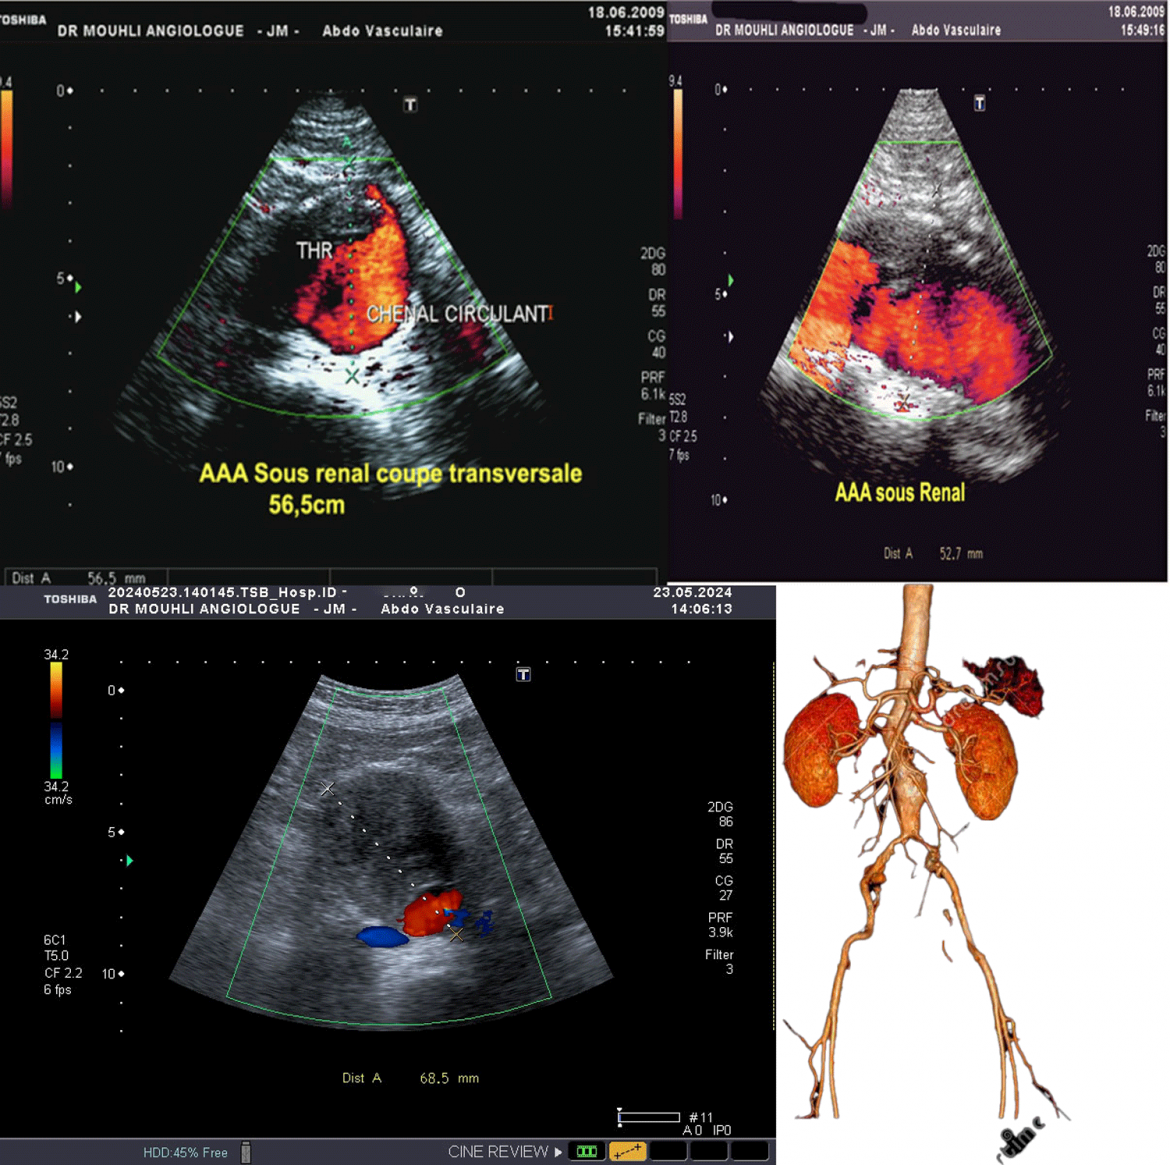

Le diagnostic d’anévrisme repose sur différents examens médicaux. L’échographie, par exemple, permet de détecter ceux qui se trouvent au niveau de l’aorte abdominale. L’angiographie, qui consiste à injecter un produit de contraste dans les vaisseaux sanguins pour les rendre visibles sur une radiographie, peut être utilisée pour détecter un anévrisme cérébral. D’autres examens, comme la tomodensitométrie (TDM) ou l’imagerie par résonance magnétique (IRM), peuvent également être utilisés.